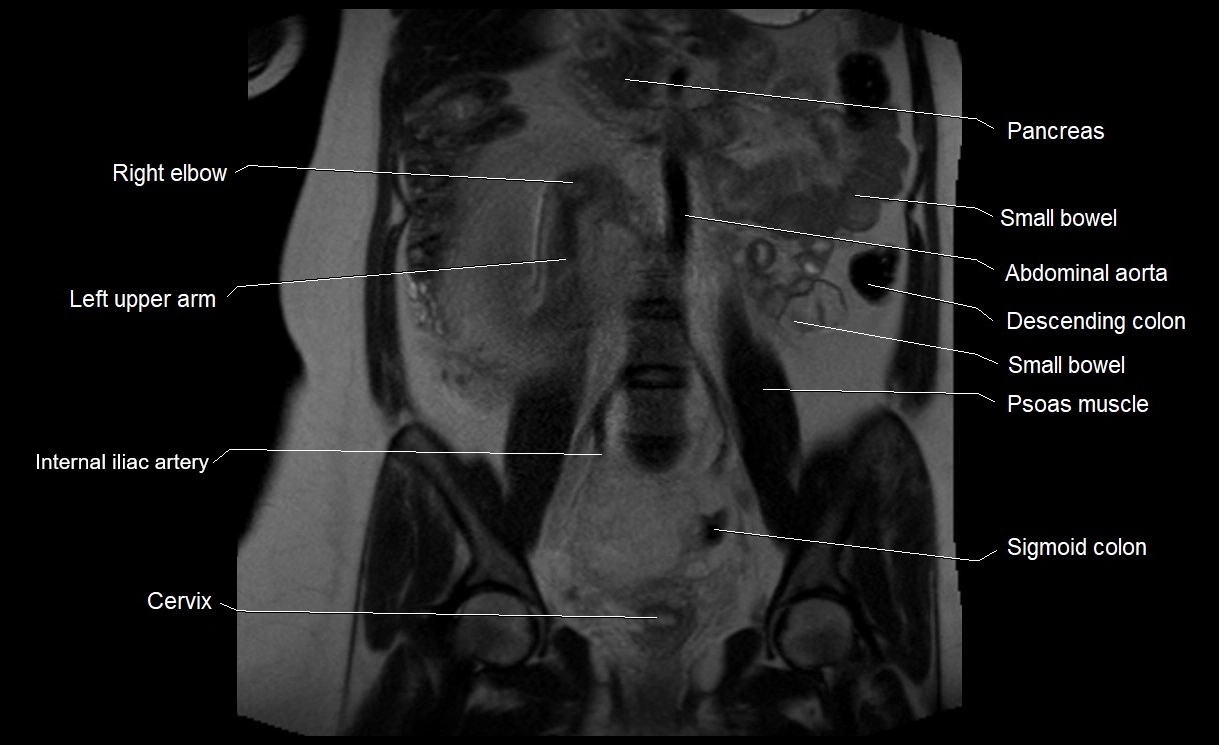

MRI Appearance

T2 HASTE (T2 GRE):

• Amniotic fluid shows very bright hyperintense signal

• Provides natural contrast against fetus and placenta

MRI image

image